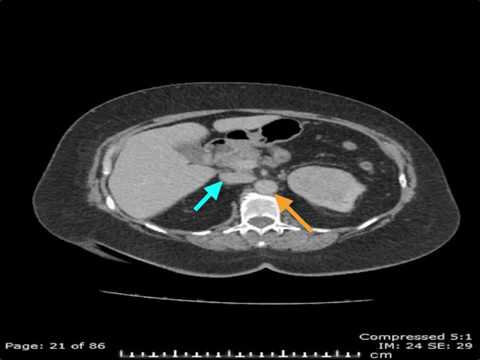

How to read a Renal Mass CT